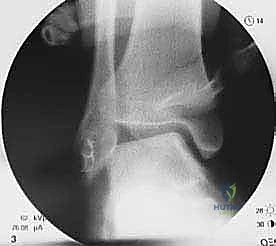

- TECH FIG 4 • (continued) J. Graft position is supported by a fibular bone bridge. (Without a bony bridge, the graft could subside and thus loosen in the soft cancellous bone trough.) K. Finished anatomic ligament weave featuring ATFL and CFL reconstruction. L. Postoperative stress radiograph. Note that there is no talar tilt.

Coughlin et al4,5 reported on 2-year follow-up in 28 patients. All patients were rated to have good or excellent outcomes with objective improvement in talar tilt measurements (13 degrees preoperatively vs. 3 degrees postoperatively) and anterior drawer testing (on average, 10 mm preoperatively vs. 5 mm postoperatively).